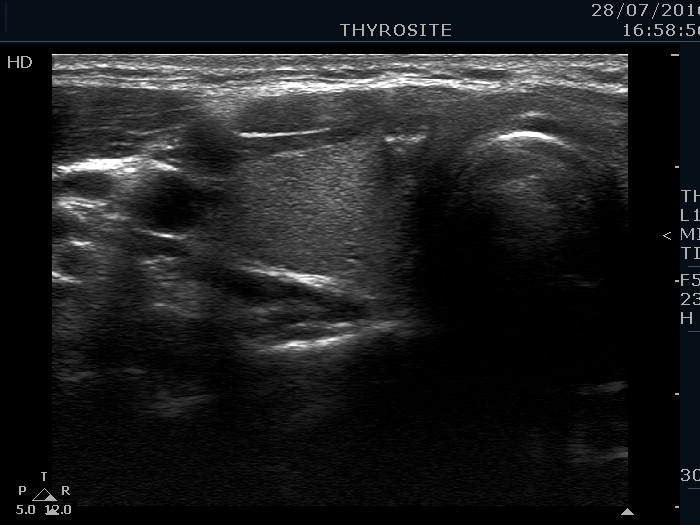

Ultrasonography. The thyroid was echonormal and had two hypoechoic nodules, one in the right and another in the left lobe. Both lesions had macrocalcifications. The nodule in the right lobe showed taller-than-wide shape and had microcalcifications while the lesion in the left lobe did irregular borders.